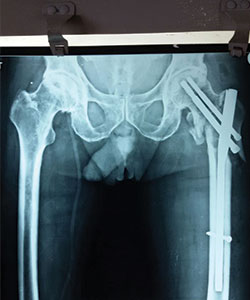

Case 3: Comminuted hip fracture

Comminuted left hip fracture in a 81 years old male patient

X-RAY 1

pre operative x-ray showing comminuted left hip fracture

X-RAY 2

Post operative x-ray (PFN done)